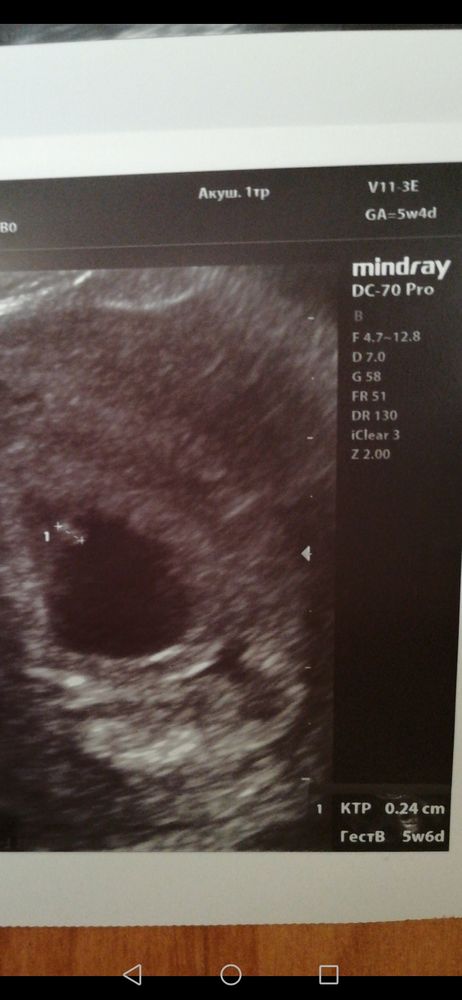

Изображение Вот нашла первое узи, срок почти 6 недель. Получается 2,4 мм ктр, а как желточный мешочек обозначается не знаю